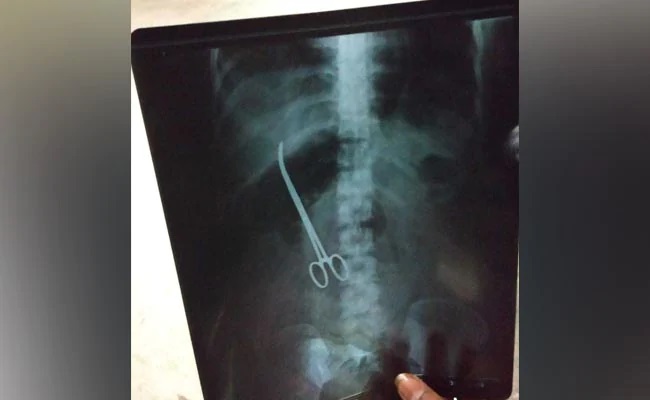

চিকিৎসক ভুল করে পেটের মধ্যে ডাক্তারি ছুরি-কাঁচি রেখেই সেলাই করে ফেলেছিলেন। মাস খানেক পরে এক্স রে করাতে রোগিনীর পেটের ভিতরে ধরা পড়ল অবহেলার এই নজির। ভারতের হায়দরাবাদের একটি হাসপাতালে তিনমাস আগে অস্ত্রোপচারের জন্য ভর্তি হয়েছিলেন ওই মহিলা। চিকিৎসকেরা অস্ত্রোপচারের সময় ডাক্তারির বিশেষ কাঁচি বা ফরসেপ রোগিনীর পেটের ভিতরেই রেখে বেমালুম ভুলে যান। তিন মাস ধরে রোগিনীর পেটেই ছিল ওই ফরসেপ।

পরীক্ষা নিরীক্ষার জন্য ফের তাঁকে ওই হাসপাতালেই নিয়ে যাওয়া হয় এবং এক্স রে করানো হয়। এক্স রে রিপোর্ট দেখেই চক্ষু চড়কগাছ তাঁর আত্মীয়দের এবং চিকিৎসকদেরও। ওই রিপোর্টেই দেখা যায় মহিলার পেটের মধ্যে রয়েছে একটি ডাক্তারি কাঁচি। অবিলম্বে তাঁকে হাসপাতালে ভর্তি করা হয়। আজ সকালেই ফের অস্ত্রোপচার করে ওই যন্ত্রটি বের করা হয়।